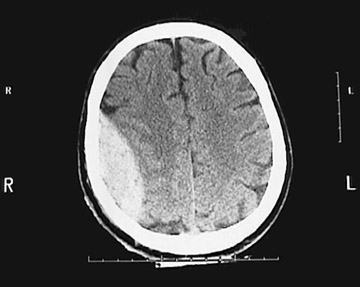

Click on the epidural hematoma in the CT scan above:

This is an axial head CT scan without contrast demonstrating a large epidural hematoma with right to left shift and ventricular narrowing. In the image below, the top of the skull is removed to reveal the middle meningeal artery which has emerged from the foramen spinosum to branch over the surface of the dura.